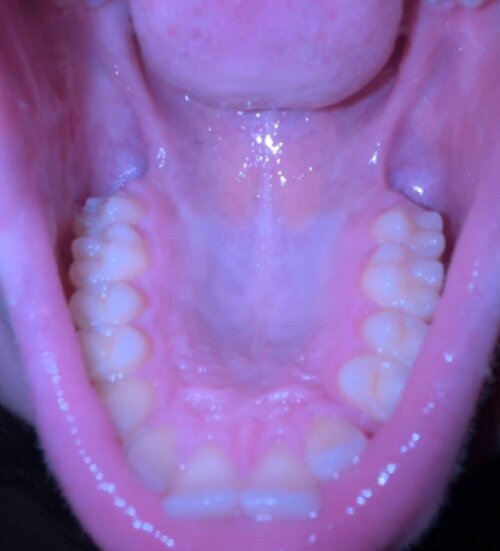

One of my fangs grew not on the line of tooth growth but just on top, but two dental clinics offered to put it in place without MARPE and only one offered MARPE so idk. Is that a narrow palate or not?

My mouth is super small so my nose to lips ratio is hell and my ipd is like 0.46 which is close to ideal i guess. Im scared that marpe would make my eyes close set and nose even bigger than my mouth width is that possible? also my midface is long and ive heard it could expand maxilla vertically for some mms which is also scary for me.

Your palate looks pretty narrow, but with marpe your nose doesnt only get bigger your upper lip also gets bigger (I think). You will be good if u get it ans same your ipd